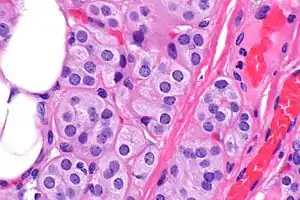

| Microscopic image of a thyroid adenolipoma | |

Adenolipomas are diagnosed by surgical resection and examining the tumor with a microscope.[5] The presence of eccrine sweat glands are used to distinguish the tumor from a common lipoma. Size and the development of the capsule (tissue surrounding the tumor) can also aid in diagnosis. [6]